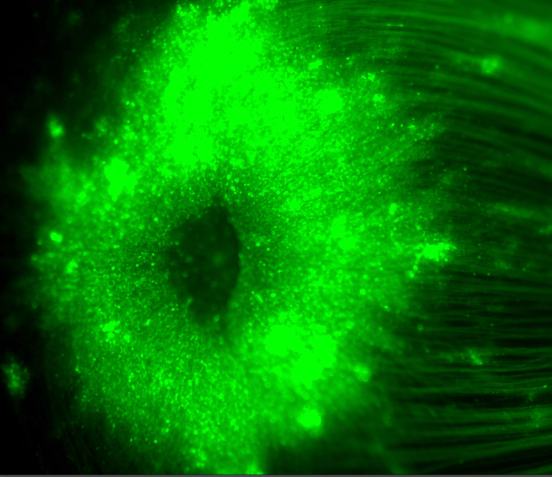

ATX027

Optimized for intravitreal delivery, resulting in robust pan-retinal expression across all regions of the retina, including fovea and periphery. 19x increase in cells transduced compared to clinical-stage 7m8. 33x increase in cells transduced compared to AAV2.

Fluorescent microscopy image of a flatmount of a retina transduced by AAVs expressing GFP.